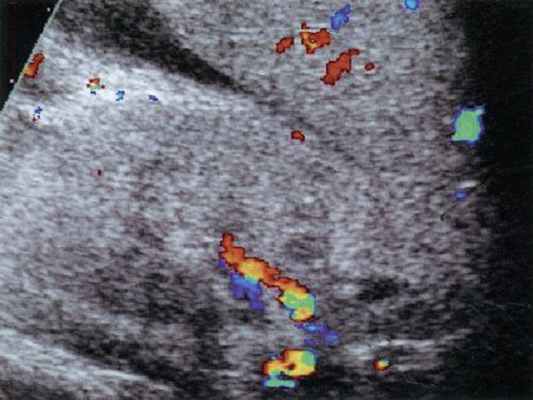

Для ангиотромботической фазы характерно резкое обеднение ренального кровотока. Обычно удается визуализировать только магистральные и сегментарные почечные сосуды, иногда - начальные отделы интерлобарных ветвей (рис. 1а). Для почки здорового ребенка того же возраста (рис. 1б) характерна возможность визуализации кровотока вплоть до субкапсулярного уровня, хорошо визуализируется кортикальный кровоток.

Рис. 1. Сравнение ренального кровотока при дуплексном допплеровском сканировании у больного гемолитико-уремическим синдромом и здорового ребенка того же возраста.

а) Дуплексное допплеровское сканирование почки здорового ребенка трех лет.

б) Дуплексное допплеровское сканирование почки ребенка с гемолитико-уремическим синдромом.